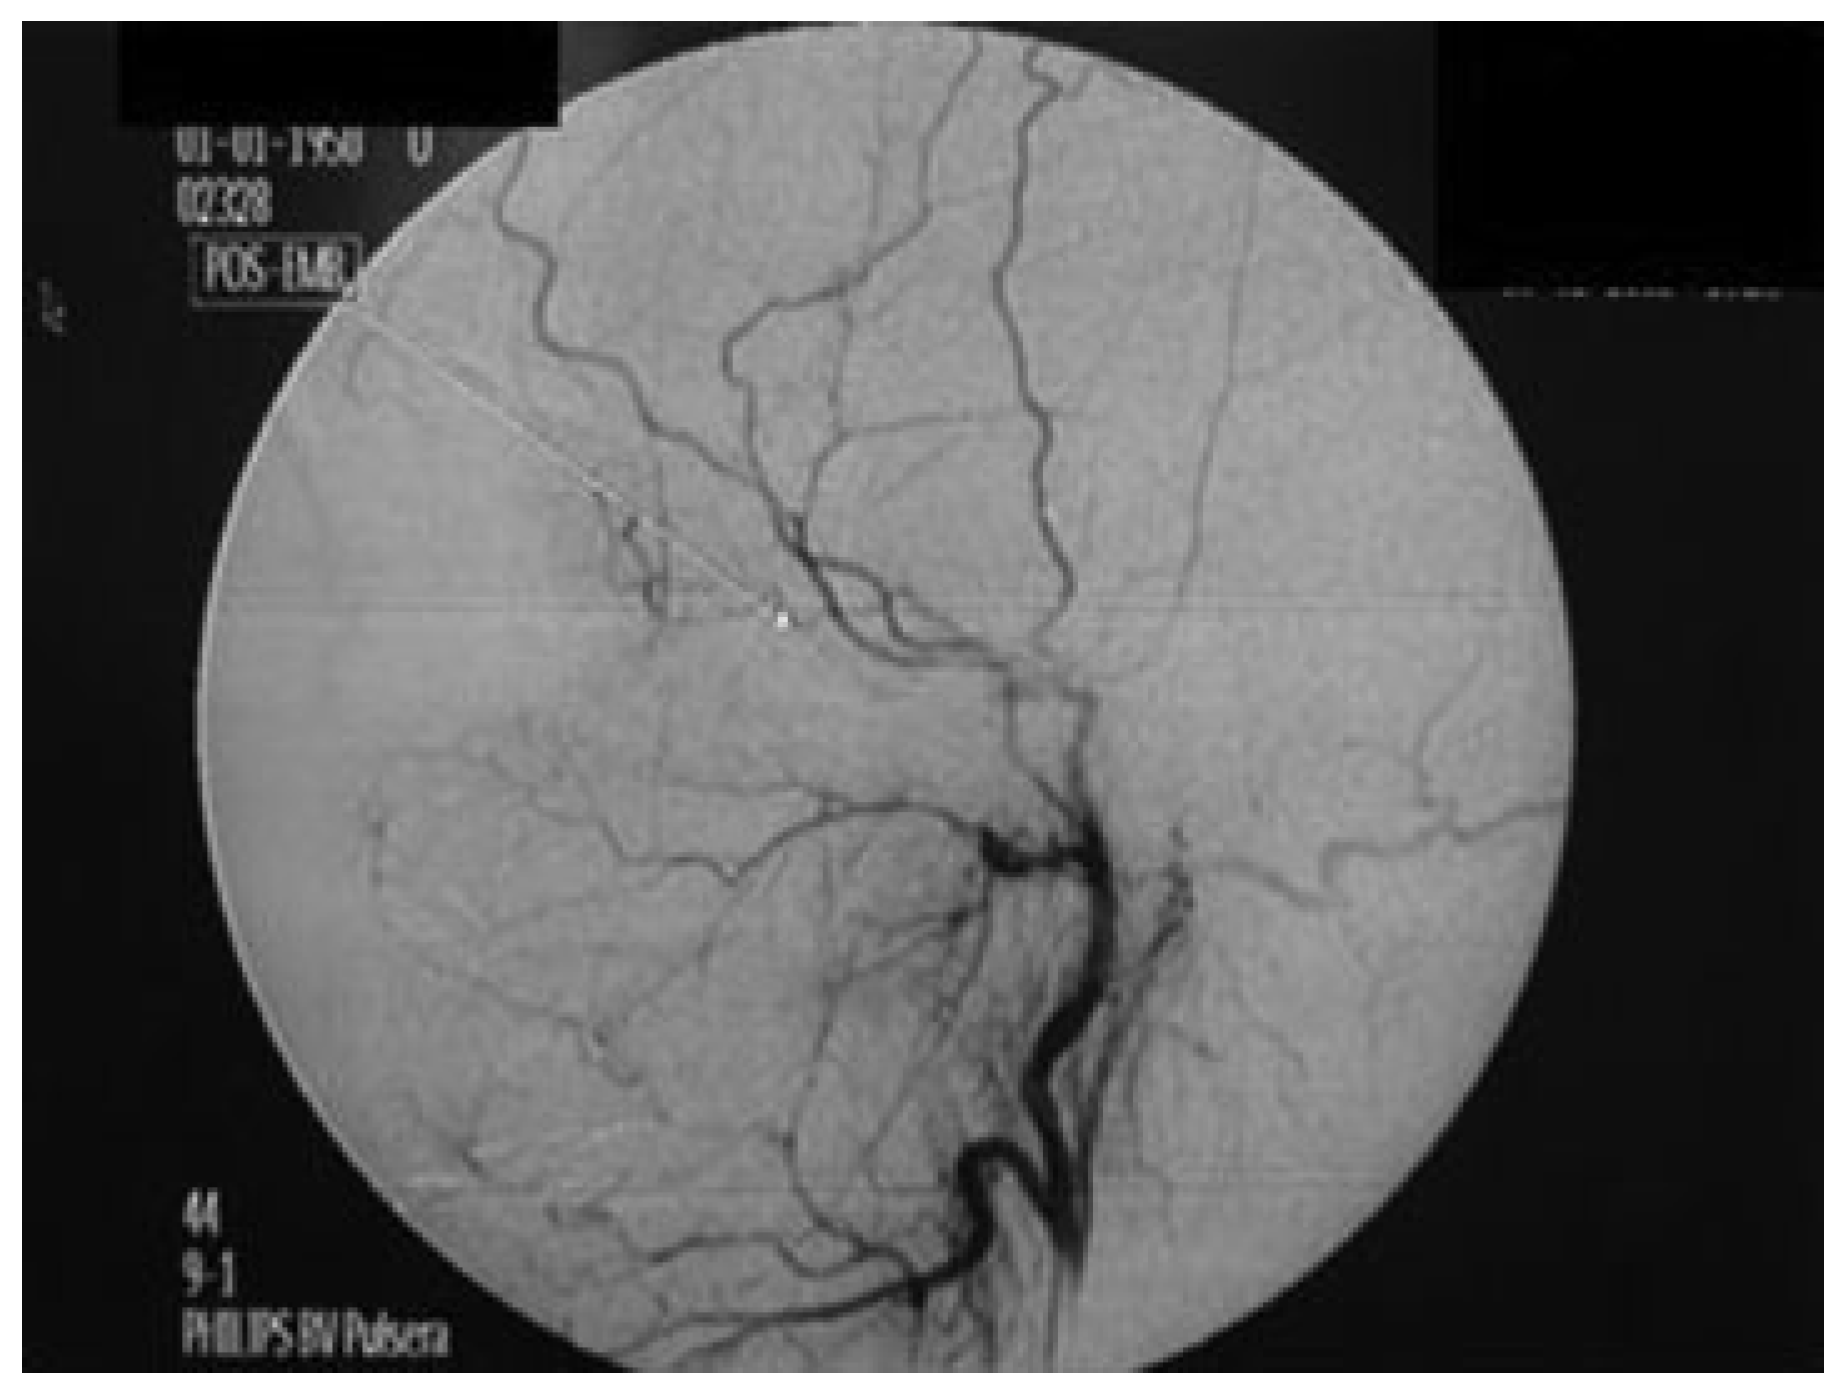

Treatment of Pseudoaneurysm of Internal Maxillary Artery: A Case Report

:Case Report